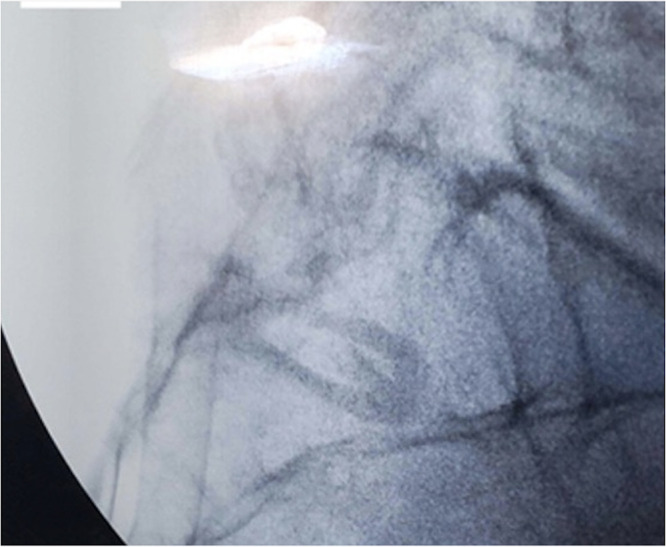

Purpose: Sacroiliac (SI) joint dysfunction accounts for 15% to 30% of reported low back pain. Primary treatments of SI joint dysfunction include medications, bracing, physical therapy, injections, and ablations. When primary non-surgical treatments are unsuccessful, fusion or stabilization may be considered. Here, we report a multicenter study aimed to evaluate real-world outcomes of posterior sacroiliac joint fusion using cortical allograft across six United States clinical sites.

Methods: Patients diagnosed with sacroiliitis through physical examination and diagnostic injection who have failed conservative management that ultimately underwent percutaneous allograft implant with at least 6 months of follow up were included. Data extracted from electronic health records included demographic and clinical characteristics, Numeric Rating Scale (NRS) pain scores, and patient-reported adverse events. Descriptive statistics were utilized to summarize baseline characteristics, and proportion of patients achieving minimally clinically important difference (MCID) was assessed. Paired t-tests were employed to compare pre-operative and post-operative outcomes.

Results: A total of 258 patients were included. Of these, 63.9% were women and 36.1% were men, with a mean age of 69.2 years and an average body mass index of 29.6 kg/m². Average NRS at baseline was 7.61 ± 1.64 and 1.60 ± 1.86 (p < 0.05) at last follow-up visit. The mean pain reduction from baseline to the last follow-up (91.2 week mean or 1.75 years) was 6.01 points, exceeding MCID. The safety profile was favorable, with no serious adverse events reported in this cohort.

Conclusion: Our findings affirm that posterior SI joint fusion constitutes an effective and enduring treatment option for patients suffering from SI joint dysfunction unresponsive to conservative care. The results indicate that posterior SI joint fusion is safe and effective at achieving sustained pain relief. Our findings are congruent with previously published studies and provide further evidence of sustained durable pain outcomes.